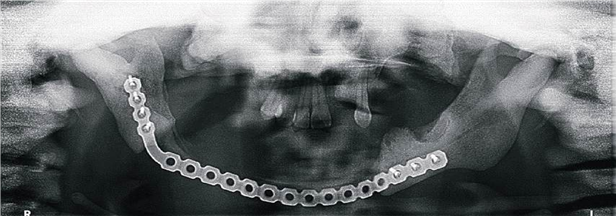

En las figuras 6 y 7 se aprecian las imágenes postquirúrgicas de la ortopantomografía y reconstrucción tomográfica respectivamente. Se observa la placa de reconstrucción fijada con 7 tornillos.

Figura 6. Ortopantomografía postquirúrgica.